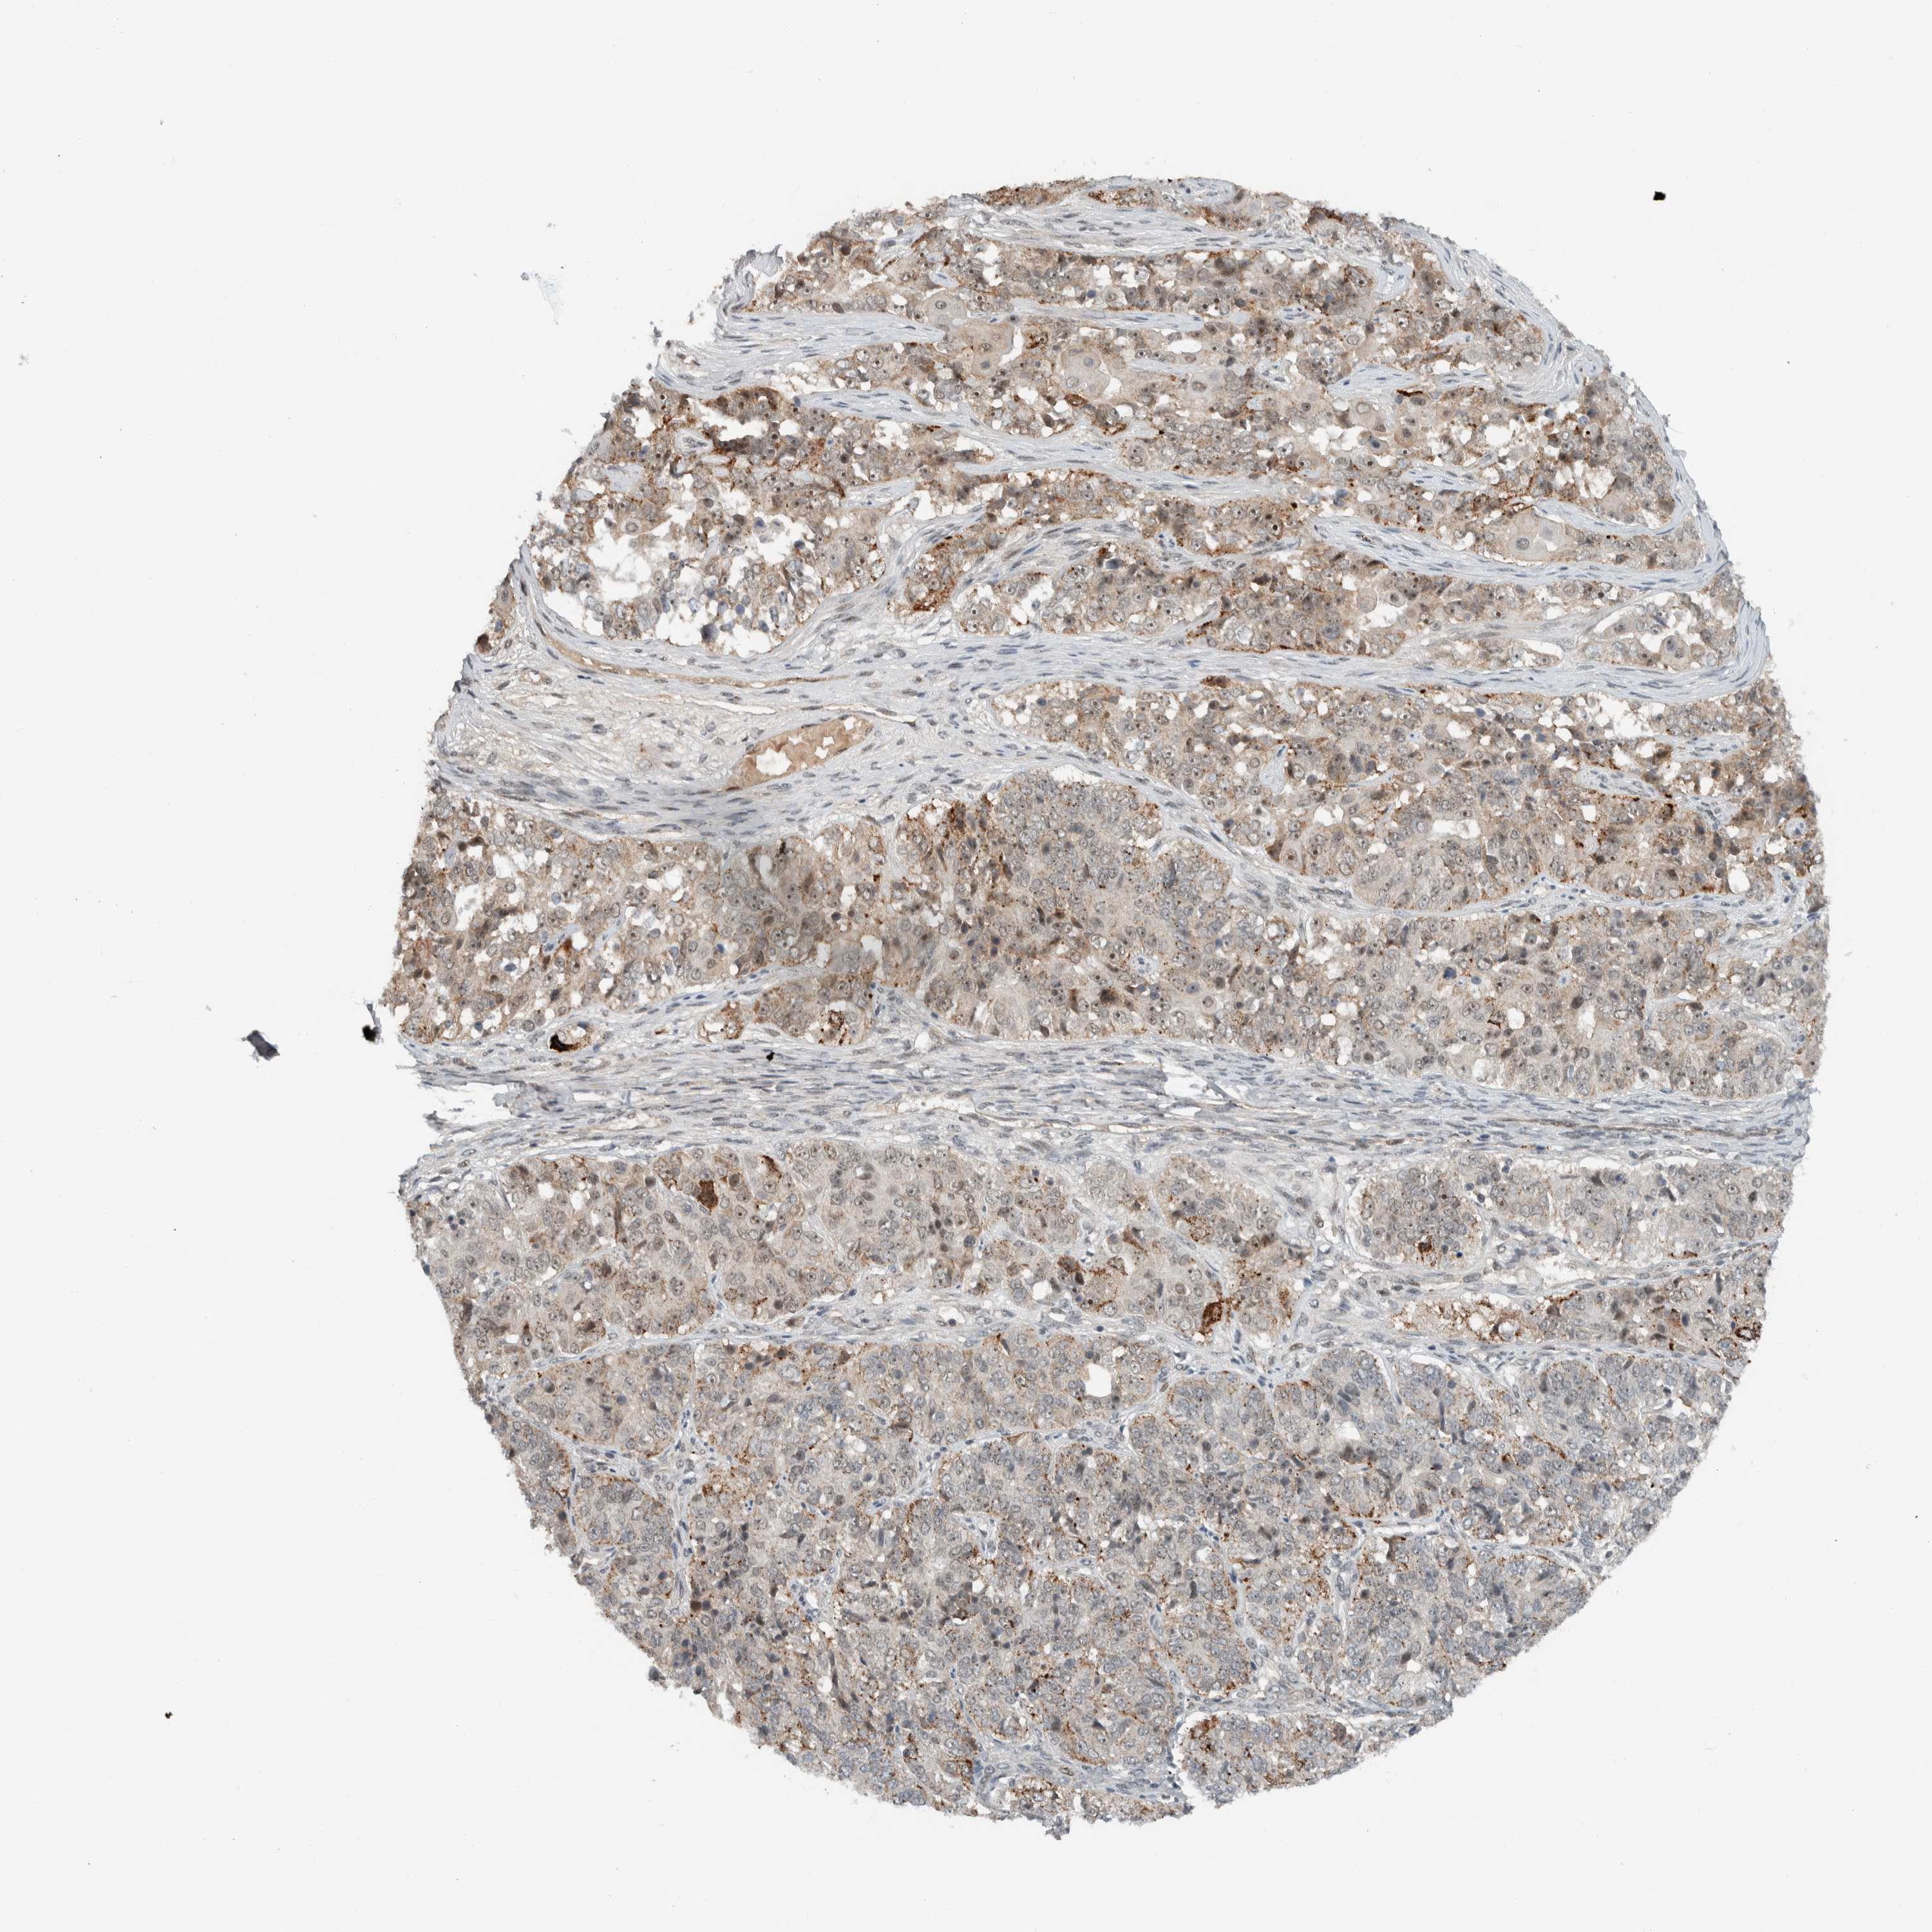

Antibody HPA024037

Antibody HPA065325

Staining

High

Medium

Low

Not detected

Intensity

Strong

Moderate

Weak

Negative

Quantity

>75%

75%-25%

<25%

None

Location

Nuclear

Cytoplasmic/membranous

Cytoplasmic/membranous,nuclear

Cystadenocarcinoma, serous, NOS

Carcinoma, endometroid

Cystadenocarcinoma, mucinous, NOS

Carcinoma, NOS